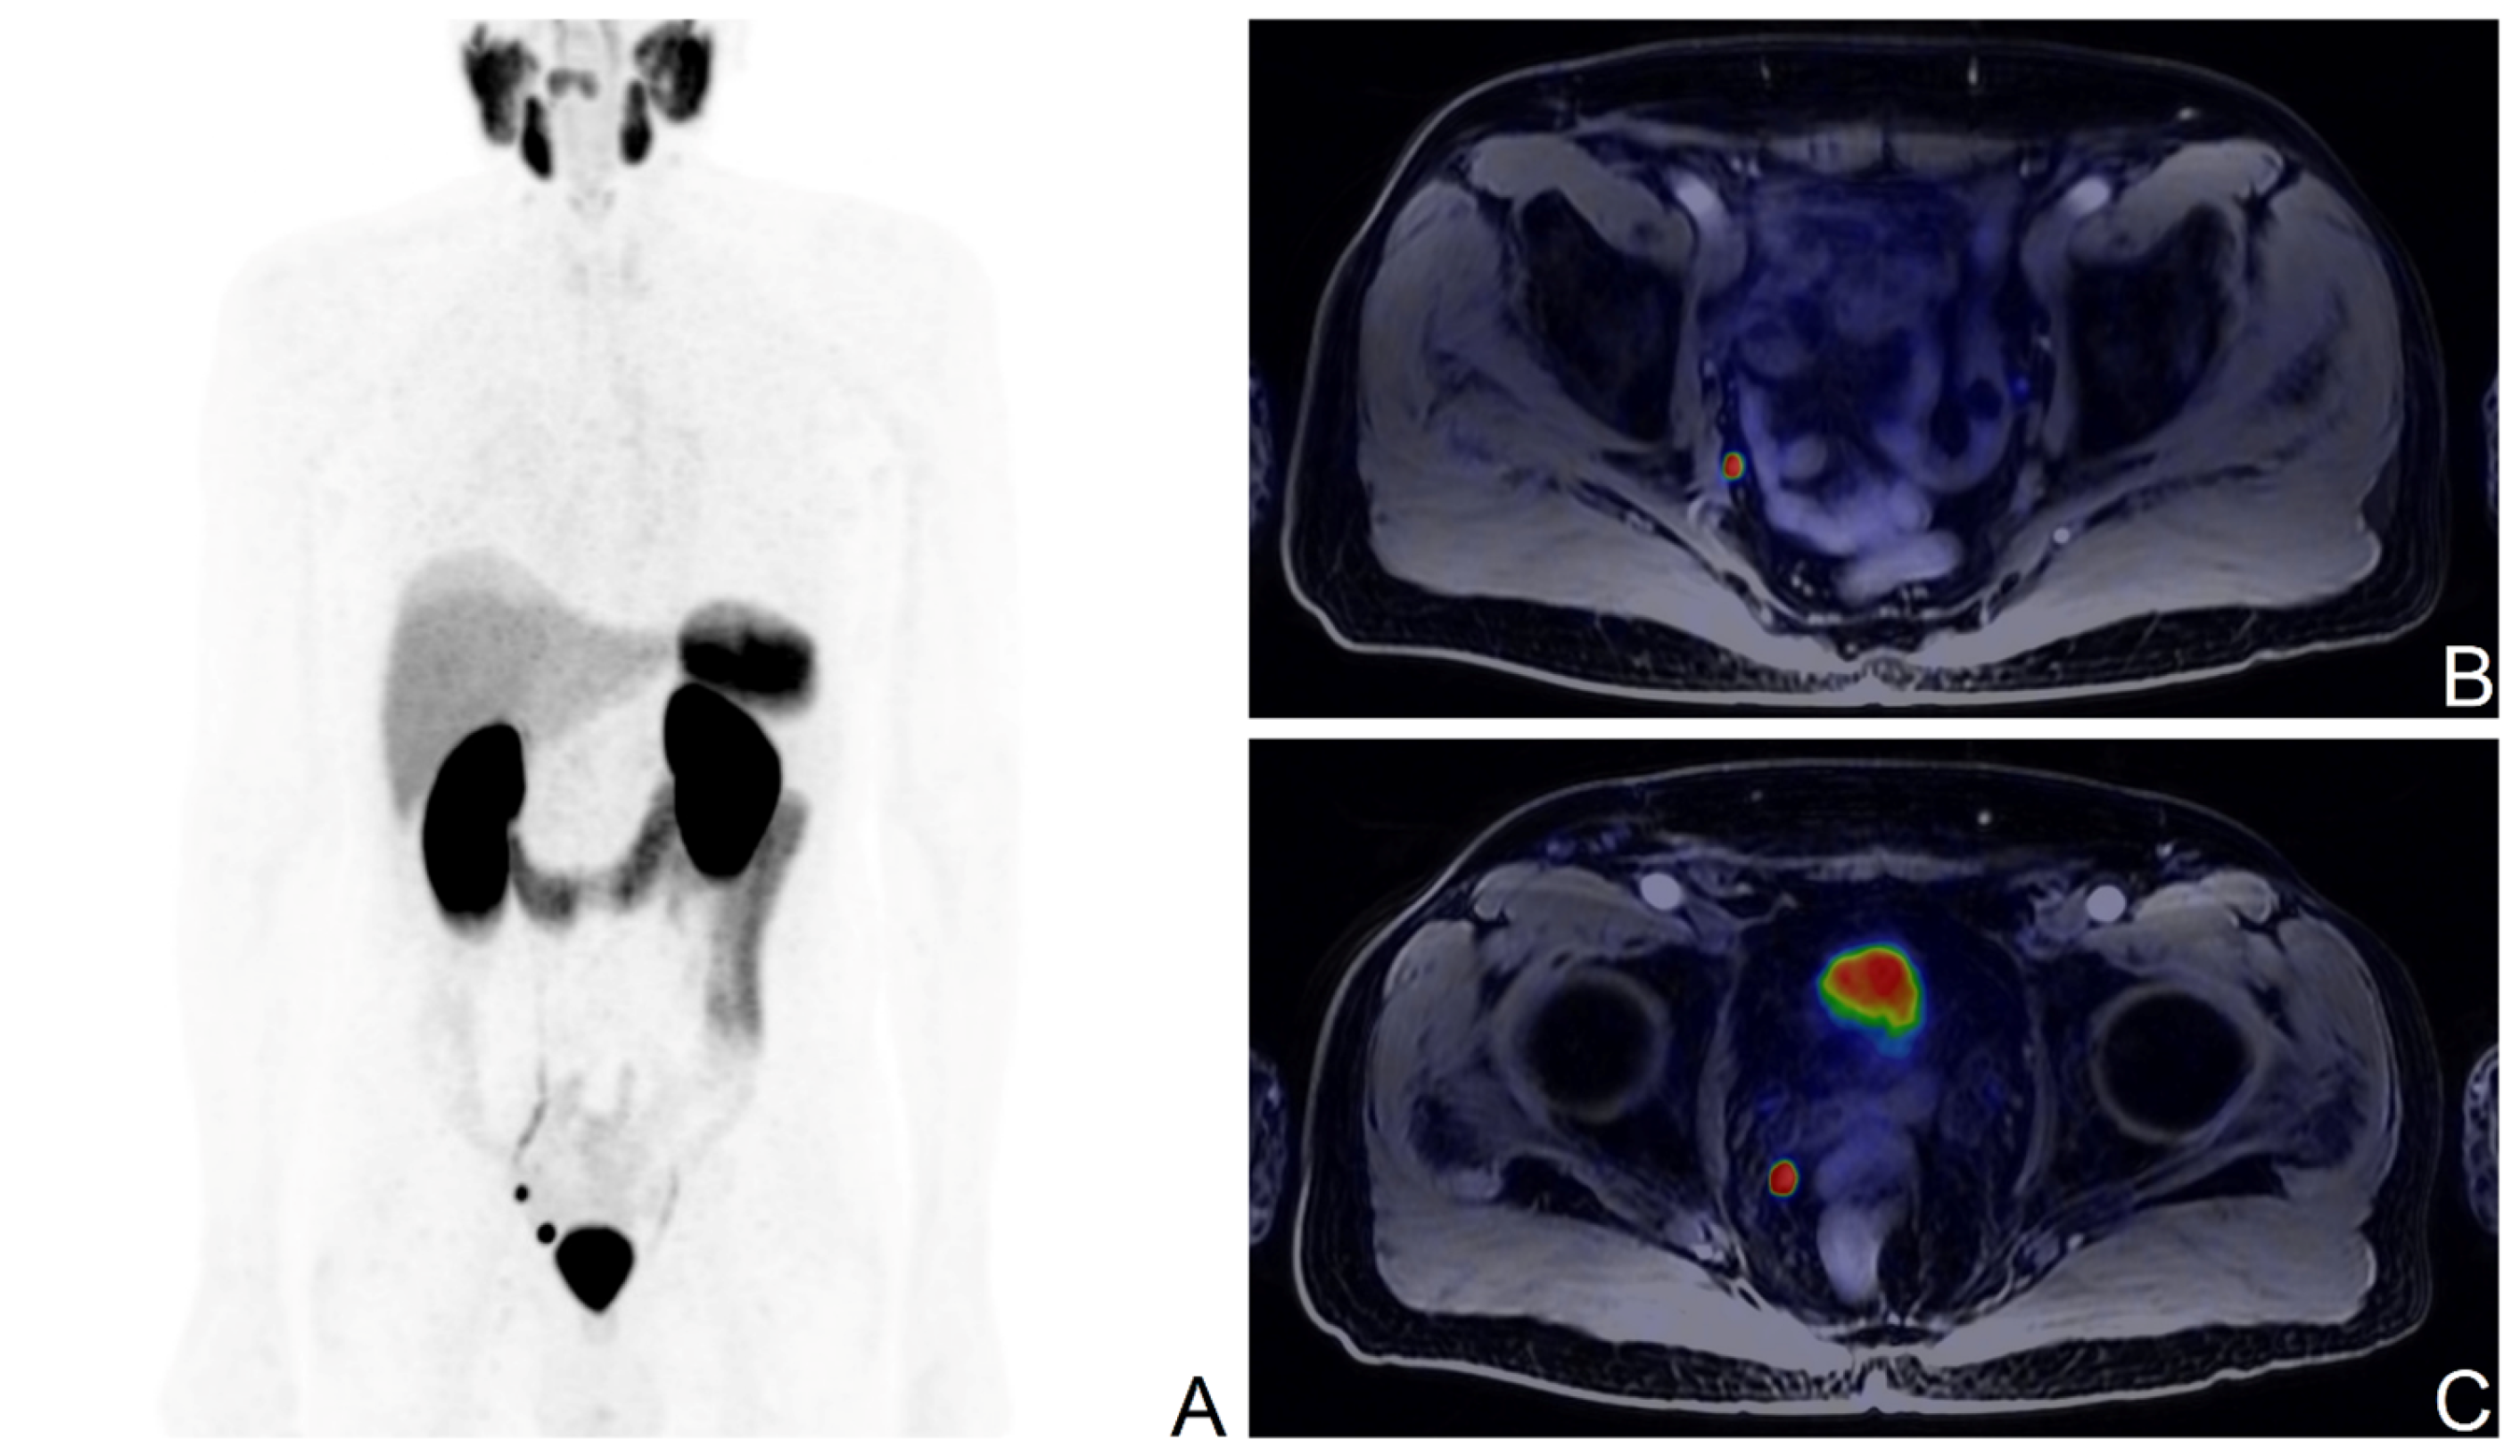

3.2. PET Findings

3.3. Validation of [68Ga]Ga-PSMA-11 PET Findings